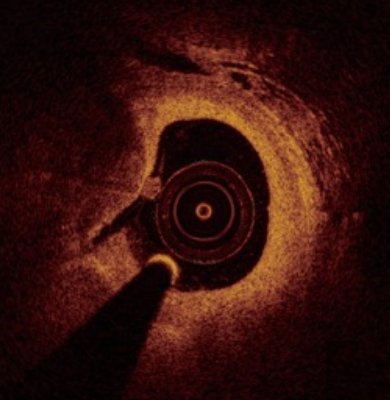

光学相干断层成像OCT)是一种高分辨率的冠脉血管腔内成像技术,利用近红外光照射血管壁,通过测量反射光的时间延迟和强度,生成高分辨率的横断面图像。OCT的分辨率可达10-20微米,比传统的血管内超声(IVUS)高10倍,能够清晰显示血管壁的微观结构。

冠脉造影显示狭窄病变             血管腔内影像显示极易破裂的斑块

血管腔内影像显示斑块侵蚀            血管腔内影像显示钙化结节